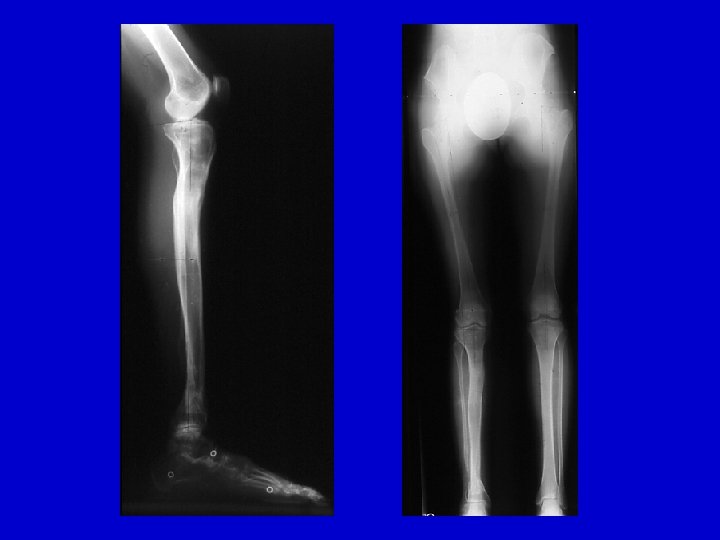

RESULTS Periosteal & Bone Grafting with IM rod and Ilizarov 1997 -2008 20 patients treated Union: 20/20

Don’t Forget Bracing until Skeletal Maturity